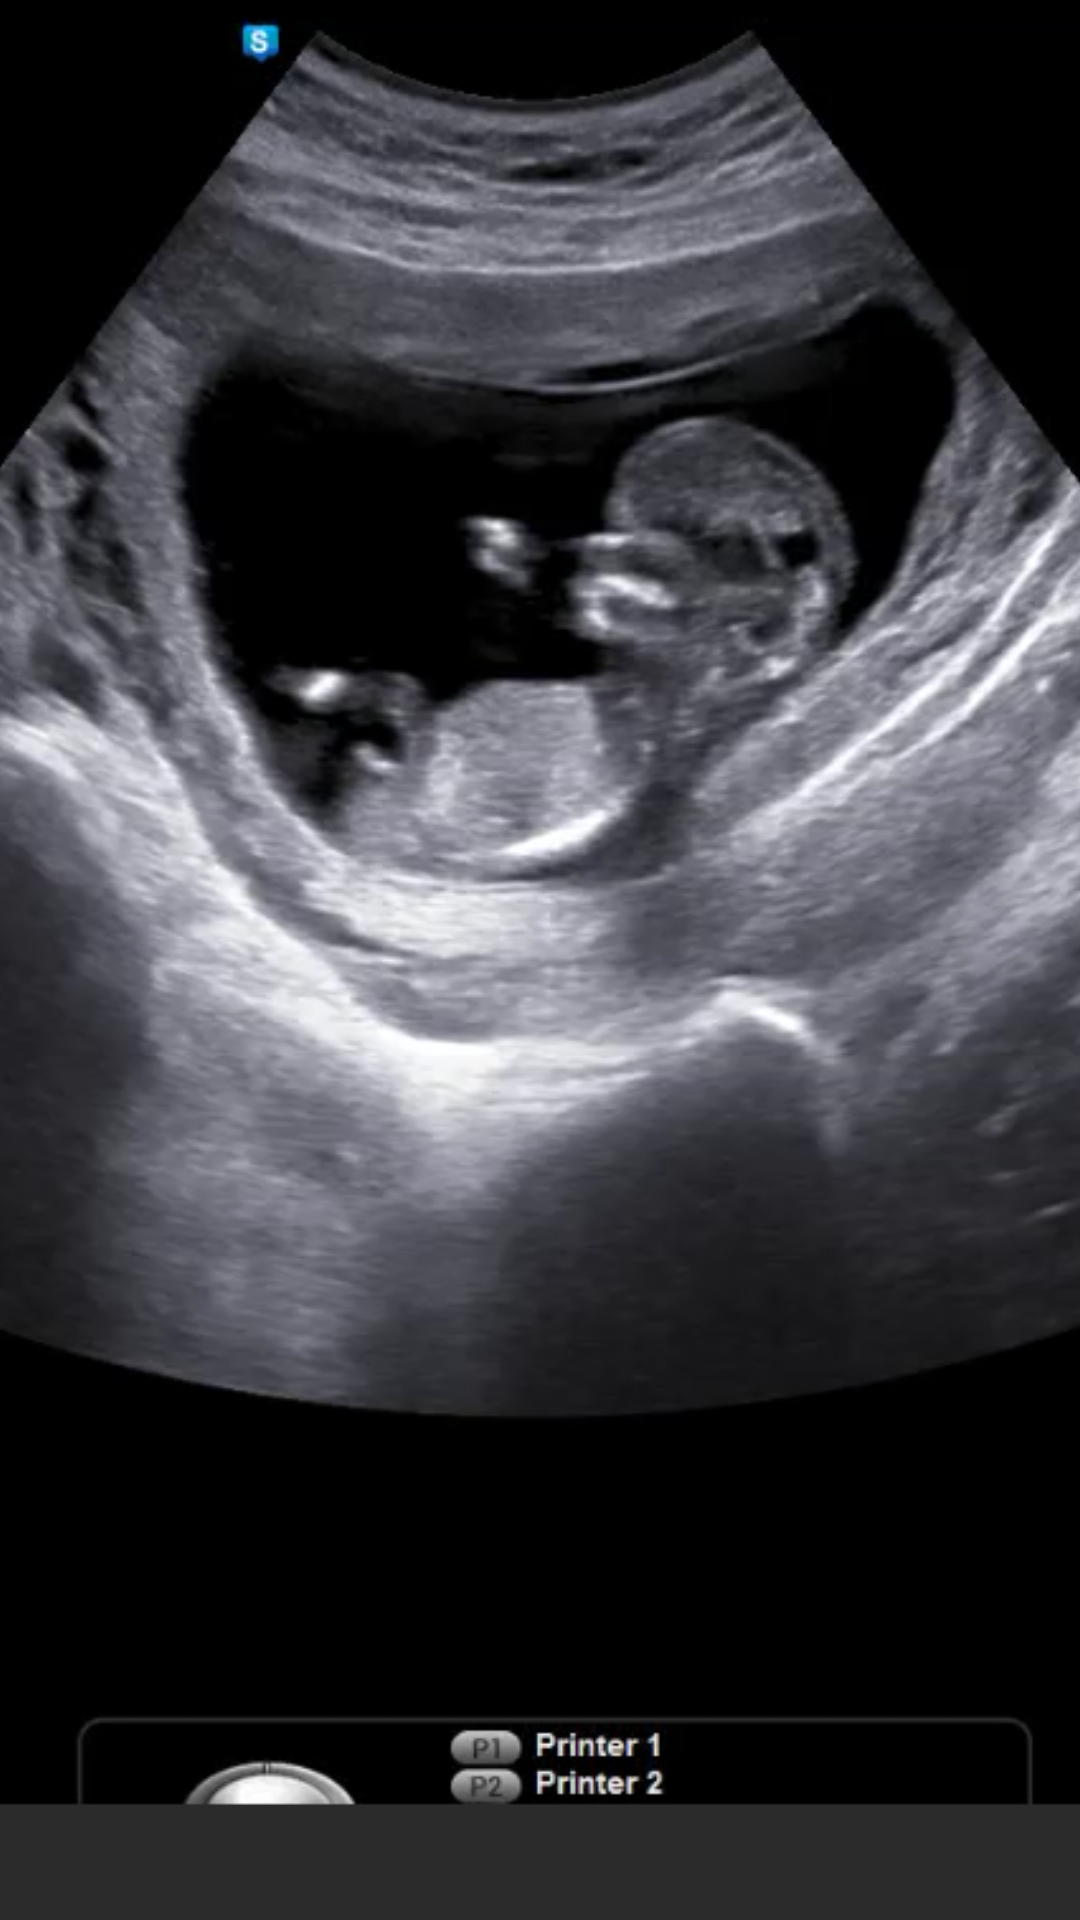

Merhabalar 11+5 günlük tahmininiz nedir acaba?

Ekli dosyalar

• IMG_6189.JPG

IMG_6189.JPG

552,4 KB · Görüntüleme: 548

• IMG_6190.JPG

IMG_6190.JPG

885,3 KB · Görüntüleme: 538

• IMG_6191.JPG

IMG_6191.JPG

918 KB · Görüntüleme: 512

Merhaba, yüklediğiniz görsellerde nub çıkıntısı görünmüyor. Bu yüzden değerlendirme yapamıyoruz. Sağlıklı gebelik geçirmeniz dileği ile..